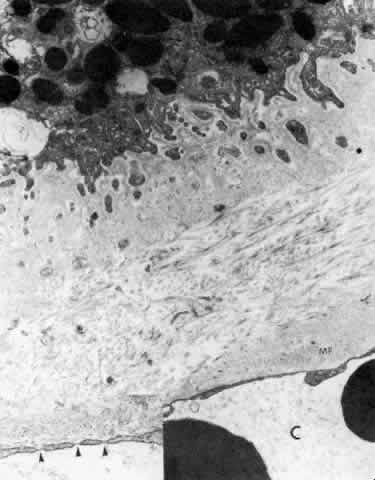

THE POSTERIOR ATTACHMENTS OF THE CILIARY MUSCLE

The posterior attachments of the ciliary muscle have been studied extensively in young and old primates (rhesus monkeys). Their elastic tendons have many associated elastic microfibrils as in the anterior tendons, but their elastin content is greater, with broader areas of more mature fibers (Fig. 43A).62 The tendons have connections to the elastica surrounding the pars plana vessels (Fig. 43B), and both have connections with the elastica of Bruch's membrane. These elastic structures are connected to each other as well as to the basement membranes of the ciliary epithelium and vascular walls by oxytalan fibers (elastic microfibrils), so that the whole complex can function as a unit.33,62,63 What percent of the tendons have direct attachments to Bruch's elastica is still somewhat uncertain, as it is difficult to follow the elastic fibers in their three-dimensional course, but the elastic network is extensive enough to support the concept of a coordinated action.

Fig. 43. Insertion of the posterior ciliary muscle (m) in the pars plana. A. Elastic tendons are seen associated with the three central thin muscle tips. The tendons are networks of elastic fibers (el), some aggregated oxytalan fibers (arrows), infrequent small elaunin fibers (arrowhead), interconnected by diffuse elastic microfibrils. Basement membranes are interrupted where tendons attach to the cells. Stained with gold-labeled elastin antibody. (X 30,700) B. Perivascular elastica (el) showing microfibrillar interconnections adjacent to a knobby Bruch's membrane (asterisk). (X 19,600) C. Bruch's membrane cut parallel to its surface, showing excrescences with attaching elastic microfibrils (asterisks) and closely associated collagen fibrils (arrows). A-C, at age 17.

The posterior tendons resemble large elastic tendons elsewhere,59 showing invagination of the terminal ends of the muscle fibers, and dense plaques on the plasmalemma with interruption of the basement membrane where the cells attach closely to elastic tissue. Aging changes in these posterior tendons, however, are quite different from those in the anterior tendons. By the second decade there are knobby excresences of elastin and dense granular material on Bruch's elastica (see Fig. 43B), some at branching sites. Other protrusions suggest attachment sites for oxytalan and elastic fibers or collagen (Fig. 43C), connecting Bruch's elastica to the pigment epithelial basement membrane and to the stromal elastica. The whole insertion region in the inner pars plana stroma increasingly becomes filled with large collagen fibers and electron-dense amorphous and granular material of a hyaline degenerate type, rather than of the banded and elastotic type seen anteriorly. This fibrotic hyalinized tissue is hypothesized to be a major cause of accommodative loss with age, as it would tend to “fix” the muscle in place, preventing forward movement, and also to reduce the amount of elastic tension available for a return to the nonaccommodated state.62